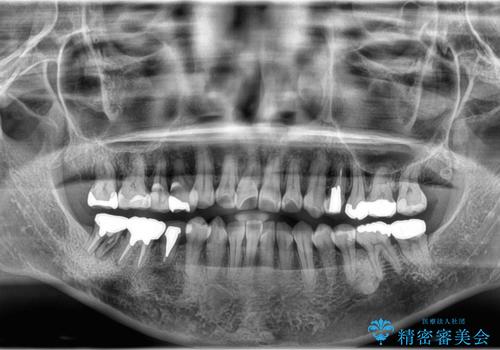

- 食事の度に、歯の中に物がつまるとのことで来院された患者様です。

精密検査を行った結果、歯が折れていたため保存は難しく、インプラント治療になりました。

現在は、違和感なども無くなり、固いものも食べられると喜ばれていました。

インプラント治療をすることによってしっかりと噛めるようになりました。